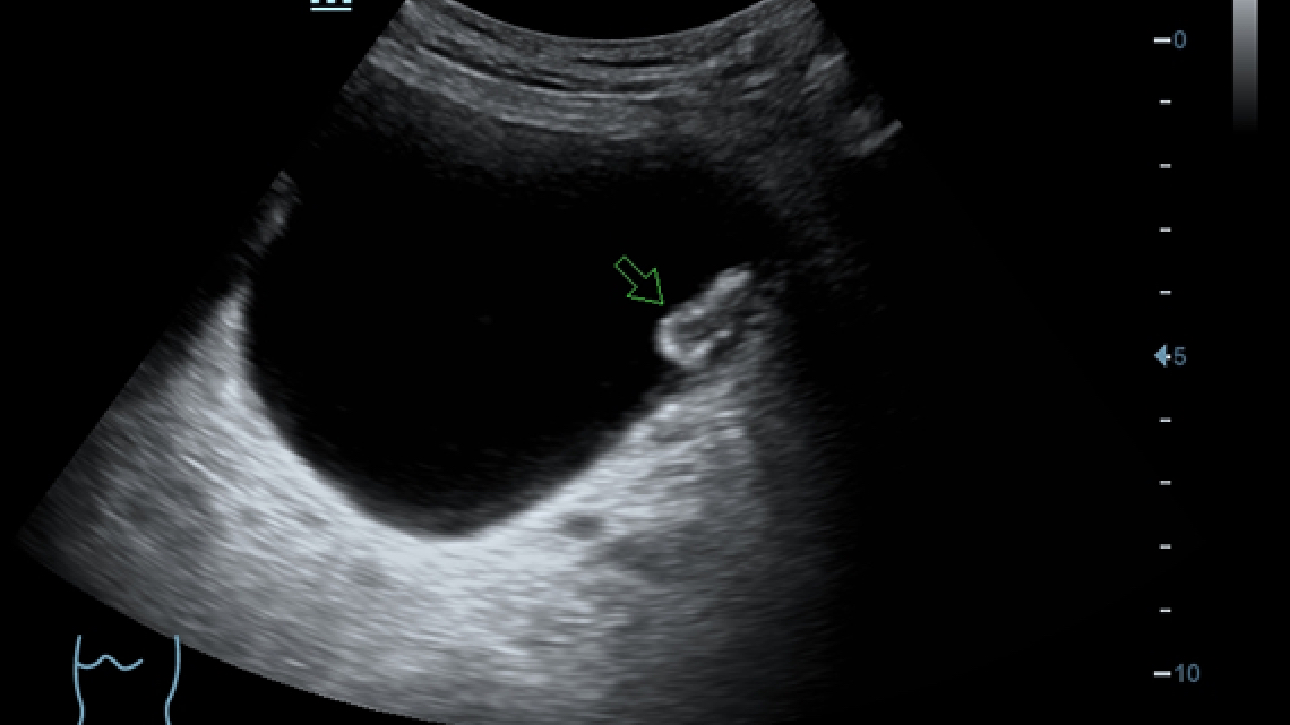

De DC-60 Exp met X-Insight is ontworpen op basis van diepgaand inzicht in klantbehoeften om hoge effici?ntie met nauwkeurige beeldverwerking te leveren, dankzij eXacte helderheid, eXceptionele intelligentie en eXcellente ervaring.

eXcellente ervaring